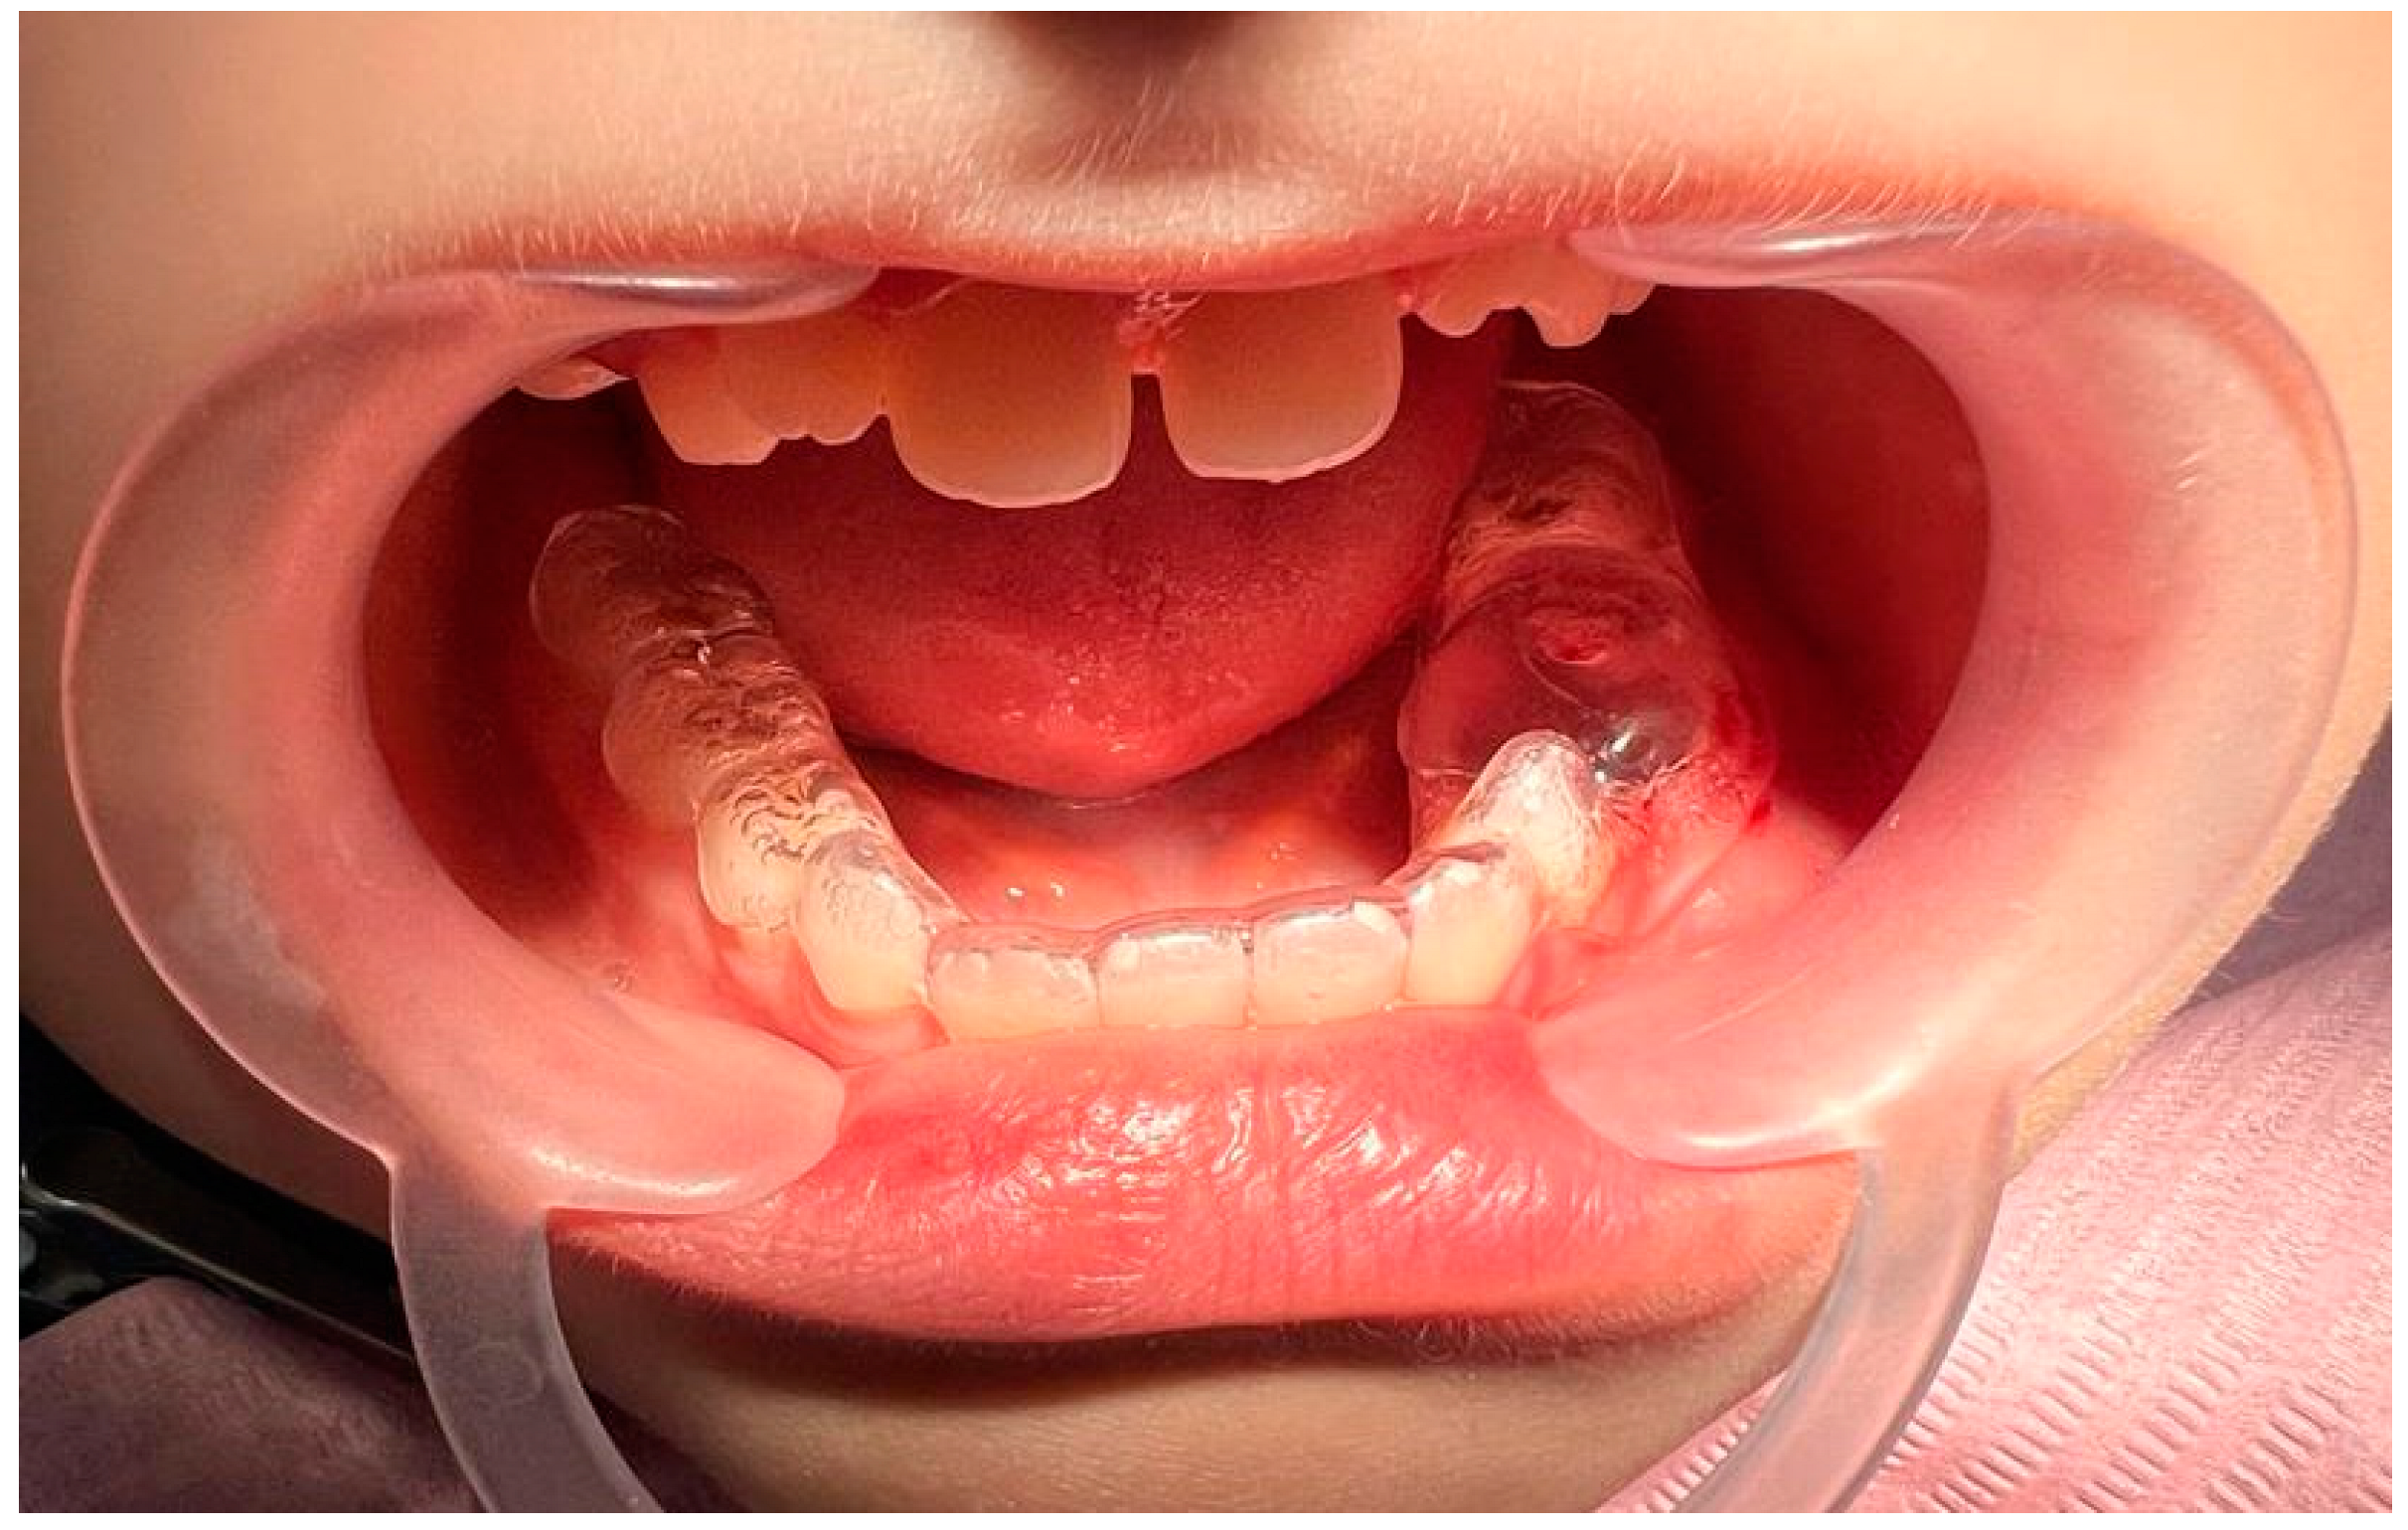

2. Case Report